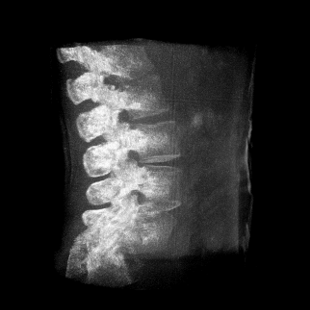

提供更大的術(shù)中三維成像視野,采集更多圖像信息,可一次拍全全段頸椎、全段腰椎、七節(jié)胸椎、雙側(cè)骶髂關(guān)節(jié)、股骨頭及單側(cè)盆骨。